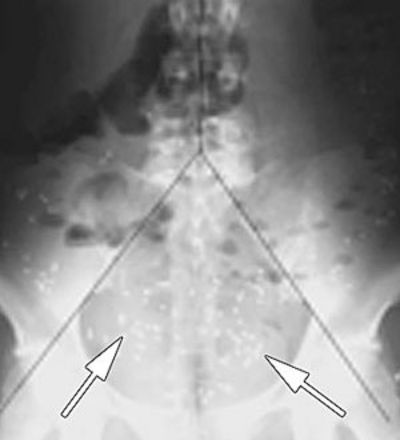

Die Transportfunktion des Dickdarms ermitteln

Bei der Kolontransitzeit-Bestimmung (KTZ) wird die Dickdarmpassagezeit gemessen. Hierfür nehmen Sie eine Woche lang täglich zwei röntgendichte Gelatinekapseln ein. Die Kapseln wandern über mehrere Tage durch den Magen und Dünndarm bis in den Dickdarm. Im Lauf dieser Zeit lösen sie sich allmählich auf. Dabei werden mehrere kleinere Markerkapseln freigesetzt.

Am Ende der Einnahmewoche erstellen wir ein Röntgenbild des Bauchraums (Abdomen). Mithilfe dieses Bildes lässt sich feststellen, ob Sie die Markerkapseln bereits ausgeschieden haben oder ob sie sich an einer bestimmten Stelle des Darms ansammeln. Eine Ansammlung der Kapseln weist auf eine Erkrankung des Darms hin. Die Methode erlaubt, verschiedene Formen von Darmausscheidungsstörungen wie chronische Verstopfung zu diagnostizieren.